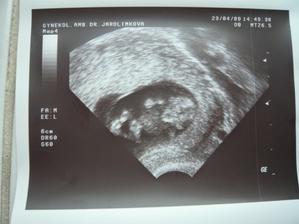

Tak se na nás snad už štěstí konečně usmálo a na IVF už nepůjdeme....... Měli jsme těsně před stimulkou na 2.IVF a čekali na mrchu. Místo toho jsme 15.3.2009 objevili naše krásné //. 17.03.2009 bylo na UTZ vidět plodové vejce, cca 2,7mm, další kontrola 31.3.2009. Tam už byl vidět náš bobeček, 6,3mm veliký a srdíčko mu bilo jako o závod. Dostali jsme krásné fotečky a jsme moc šťastní. Tak konečně je 23.4.2009 a jsme i s taťkou na dalším UTZ, jsme 9+6. Paní doktorka z nás měla velkou radost, říkala, že tak mrskající se miminko už dlouho neviděla. Velikostí odpovídáme úplně na den, máme už těhu průkajdu a dneska jsem se objednala na časný genet. skr. k MUDr. Břešťákovi. Termín porodu je 20.11.2009 a manža má narozky 24.11. 2009. No a já je mám zítra, takže super dnešní dárek. Tak dneska 11.5. 2009 jsem byla u zubaře pro razítko do těhu průkajdy a už ho mám. Další den 12.5.2009 jsme byli u mé praktické paní doktorky, natočila mi EKG a dala nám razítko do těhu průkajdy. Dneska 14.5.2009 jsme byli s manžílkem na genetickém screeningu. Pan doktor a sestřička byli moc hodní. Sestřička mi nabrala krev, vůbec jsem nezaznamenala, že je po odběru, je moc šikovná. Výsledky budou do 14-ti dnů. Pan doktor nám ukázal miminko v celé své kráse, jsme obříci, máme skoro 8 cm, NT 1,8 mm. Dle pana doktora jsme o 6 dnů větší a odpovídáme 13+5 (dle MS 12+6), tak nám upravil termín porodu na 14.11.2009. Slyšeli jsme tlukot srdíčka a bylo to nádherné, 160 úderů /min.. Pan doktor nám dal fotečky na CD, tak jsme moc šťastní. Jelikož nám pan doktor posunul termín porodu o týden dříve, tak jsme se byli 19.05.2009 zaregistrovat k porodu do FN Motol. Dneska 21.05.2009 jsme byli na kontrole a dostali jsme fotečky obličejíčka našeho mimíska. Je to celý tatínek. Mimísek na nás koukal a pěkně skotačil, paní doktorka nám ukázala jak má právě nožičku u hlavičky. Na den dětí 01.06.2009 jsme se dozvěděli, že výsledky screeningu jsou v pořádku. Jsme moc rádi. Dne 04.06.2009 jsem si volala na výsledky krevních triple testů a sestřička mi sdělila, že jsou v pořádku. Jsme s taťkou moc šťastní. Tak dneska 11.06.2009 jsme byli na kontrole u naší paní doktorky a s taťkou jsme byli zvědaví, jestli se nám už ukáže holčička nebo chlapeček. Paní doktorka se moc snažila, říkala, že by to viděla na holčičku, ale že opravdu spíše tipuje, protože miminko nechtělo roztáhnout nožičky. Tak uvidíme, jestli nám to řekne pan doktor na velkém UTZ, kam se objednáme. Bylo vidět, jak si miminko podpírá ručičkou bradičku a paní doktroka nám udělala nějaké fotečky. Jsme s tatínkem moc rádi, že se má miminko fajn. Dneska končíme 4. měsíc. Po měsíci -7.7.2009 jsme konečně zase viděli naše miminko. Paní doktorka nám ukázala močový měchýř, srdíčko, žaludek. Miminko se mrskalo, dokonce nám zamávalo. Paní doktorka nám řekla, že na 90% čekáme holčičku!